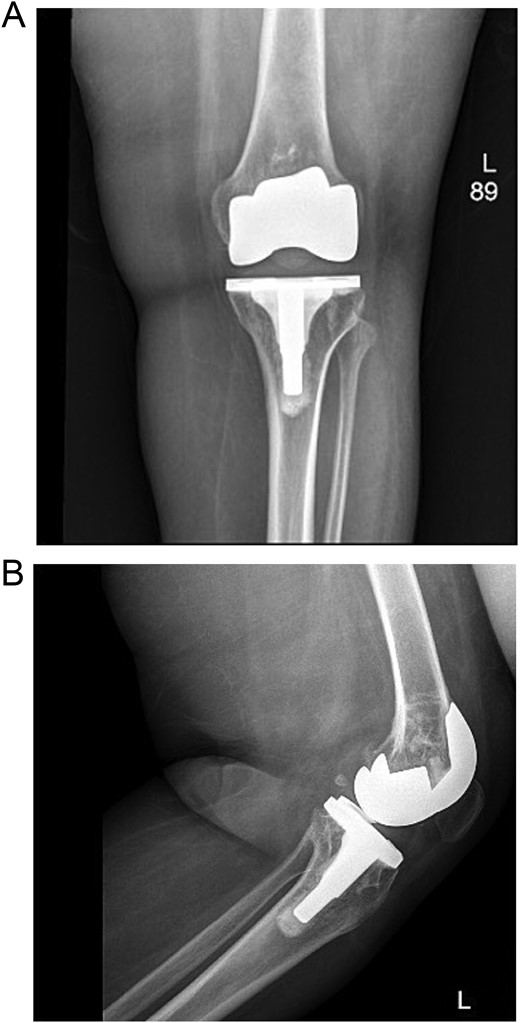

The case involves a 48-year-old obese woman with a body mass index (BMI) of 42, a known medical history of polio, and a baseline of bilateral knee hyperextension of 5º, who underwent bilateral staged TKA with posterior stabilized knee prosthesis in 2018 with a good functional level and outcome (Fig. 1).

Anteroposterior view of both knees post bilateral staged total knee arthroplasty.